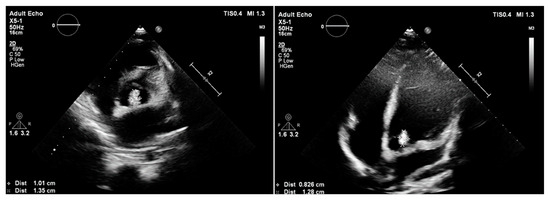

3.1. Case 1

3.2. Case 2